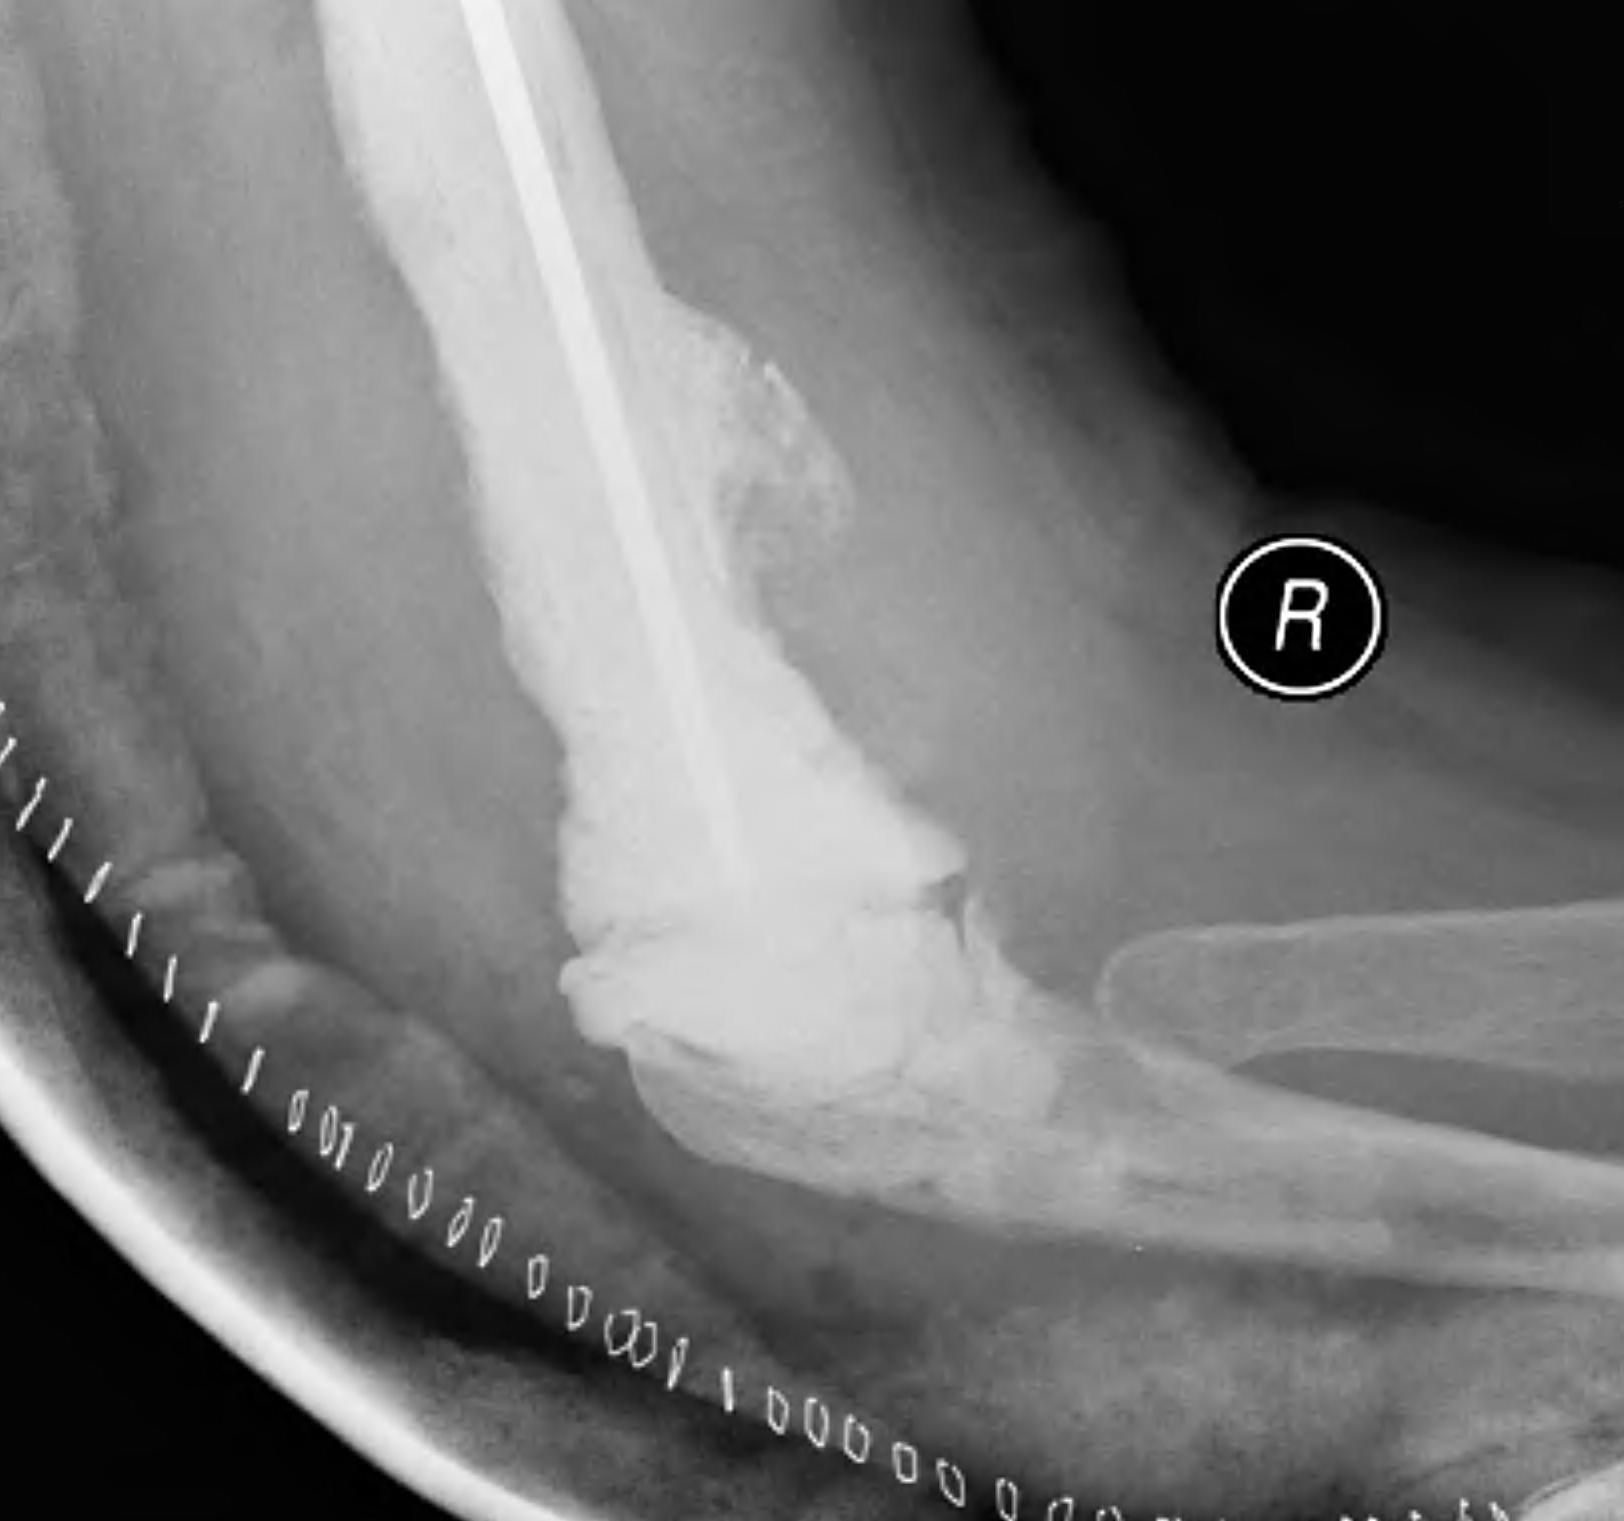

Intraoperative fracture

Humeral condyles

Ulna at risk

- slight bend / small diameter / relatively thin cortical bone

- perforations can allow cement extrusion